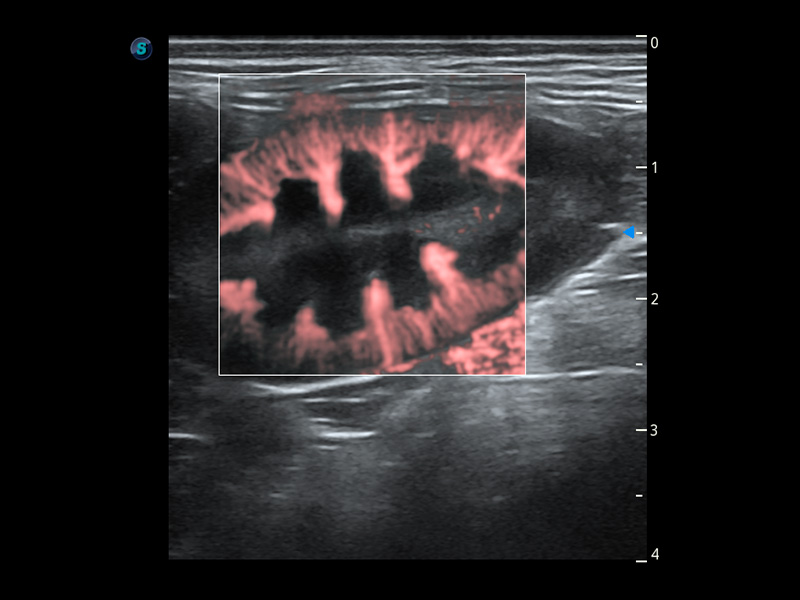

ProPet 60 作為一款高端臺式動物超聲設(shè)備,為動物醫(yī)生的日常診斷提供了一系列貼合動物臨床需求、解決臨床實際問題的高級成像功能。憑借全系列高清探頭,滿足醫(yī)生對腹部、心臟、生殖、淺表、肌骨等成像的所有需求,切實幫助您提升檢查效率,提高診斷信心。